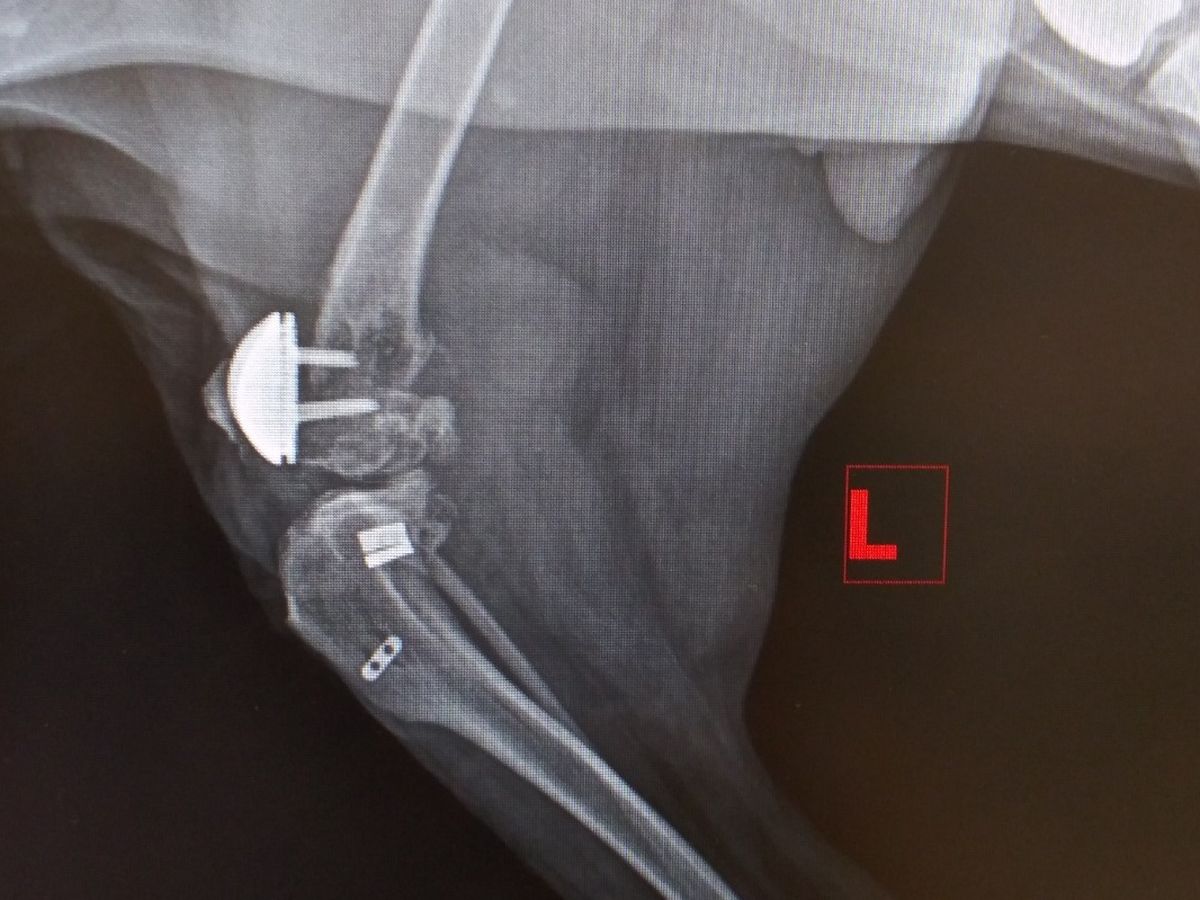

I wanted to start by saying Im sorry Ive been MIA. The flu & pink eye has made their rounds with meh human family, yuck! Thankfully everyone is almost back to 100%! Sad news today from meh vet *sigh* looong story short Im not using meh back L leg at all. Meh pawesome vet noticed this & that its super swollen so he did some xrays. Meh right is a ok. My L as you may be able to see looks like it exploded He sent the xrays to the surgeon who did meh patella replacements to see what he thinks needs to be done. At best & at the very least all the hardware has to be removed & set the femur. At worst I could loose meh leg. So moms waiting to hear from meh vet after he talks to the surgeon to get our game plan. Got a pain shot & sent home with meds & an antibiotic. Regardless of what I need done we need money to do it before I can get fixed, if anyone can help me I would be so grateful ❤